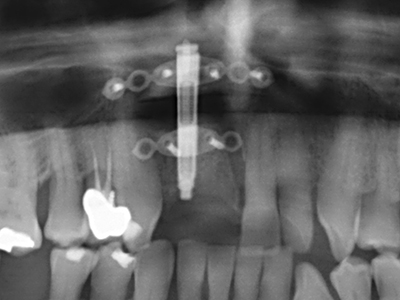

Костната тъкан е не само минерализирана структура, тя съдържа и съществено количество колагенови влакна. Това означава, че тя има не само добра компресивна сила, но и известна степен на гъвкавост, която може да се възприеме като предимство при извършване на костна аугментация. В класическата процедура по разширяване чрез костно разделяне, атрофиралият алвеоларен гребен е разделен надлъжно и внимателно разширен след достигане на подходящата остеотомна дълбочина (Фиг. 13-16), в идеалния случай без допълнително отстраняване на периостеума (Brugnami, Caiazzo et al. 2014, Stricker, Fleiner et al. 2014). Системите с винт и пластини с увеличаване на разстоянието при разширяване са доказали ефективността си при разделяне на двете костни ламели, оставайки под прага на фрактурите. В общи линии, оставащата ширина на костта от поне 3–4 mm е задължителна (Chiapasco, Zaniboni et al. 2006), за да се гарантира добра гъвкавост и достатъчно костно покритие за бъдещото поставяне на импланти. Ако е необходимо, вертикалната остеотомия на едната или двете страни може да подобри гъвкавостта. Комбинацията с допълнителни техники за аугментация, особено в букалната страна, е описана като алтернатива на класическата техника.

Процедурата по разделяне е атравматична и няма голяма загуба на пространство, използвайки пиезотриони, и няма значителна разлика между импланти в разделени челюсти и импланти в алвеоларния гребен без костен дефицит (Chiapasco, Zaniboni et al. 2006, Danza, Guidi et al. 2009). Въпреки това, важно е да има достатъчно и продължително охлаждане, особено при ограничено и дълбоко разделяне, за да се избегне термичен стрес в апикално-остеотомните зони.

Когато се извършват хирургични процедури върху кост в непосредствена близост до чувствителни структури като кръвоносни съдове или нерви, ротиращите инструменти създават значителен риск за ятрогенно нараняване. Пиезоелектрическите апарати могат да бъдат от помощ при препарация на костно покритие и отстраняване на твърда кост близо до нерви, особено за оголване на нервите след ятрогенно нараняване, както и по време на латерализация на нервите за резекционни и реконструктивни процедури или поставяне на имплант (Фиг. 17-20). Лекият контакт между пиезонакрайника и нерва по принцип не води до нараняване, но ако действате непредпазливо с трионообразни движения или приставки за остатъчен костен субстрат, може да причините временно или перманентно увреждане на нерва. Въпреки това, рискът от увреждане се счита за много по-малък, отколкото при употреба на триони или ротиращи инструменти (Pereira, Gealh et al. 2014).